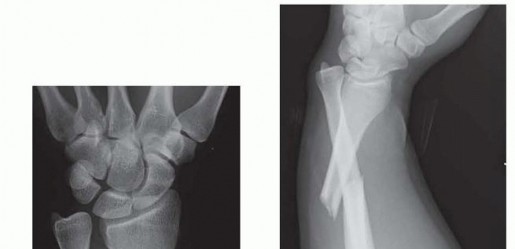

DEFINITION Distal radius fractures typically originate in the radial metaphysis and occasionally enter the ra…

DEFINITION Fracture of the radial shaft with an associated distal radioulnar joint (DRUJ) dislocation (FIG 1A…

a DEFINITION Distal radius fractures occur at the distal end of the bone, originating in the metaphyseal regi…